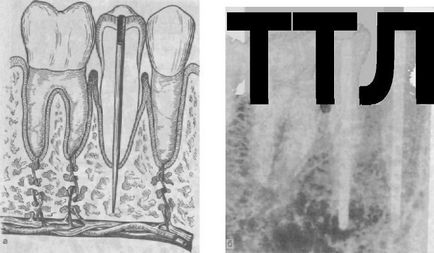

4. Endodontic implantátumok (endodonto-enossalnye) - egy csap, és a kimeneten a fejlett elülső fogak gyökércsatorna keresztül apikális lyuk a csont, hogy a mélysége 3-5,5 mm. Ezek szolgálnak rögzítés (sínbe) mobil fogak fogágybetegség. Vnutrikornevaya implantátum felülete is, intraossealis lehet menetes felcsavarozható. Endodonto-enossalnye implantátumok titánból, tantálból, KHS, alumínium-oxid (ábra. 280).

Ábra. 280. reakcióvázlat endodonto enossalnogo-graft (a); X-ray.